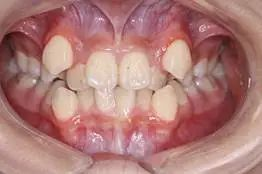

2、牙縫隙:可見前牙排列不緊密,稀疏,牙與牙之間存在間隙,嚴(yán)重影響患者的前牙美觀和容貌美觀。如圖2所示.

2,牙齒排列稀疏,存在間隙